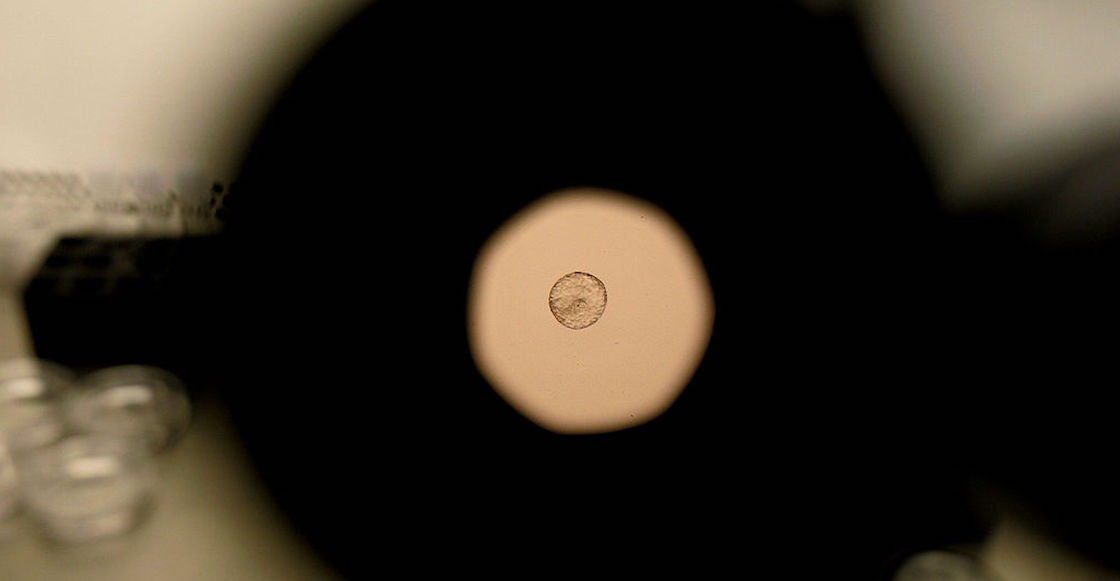

“Vista de un embrión humano donado bajo un microscopio en la Clínica de FIV de La Jolla en La Jolla, California, el martes 28 de febrero de 2007”. Foto: Sandy Huffaker-Getty Images.